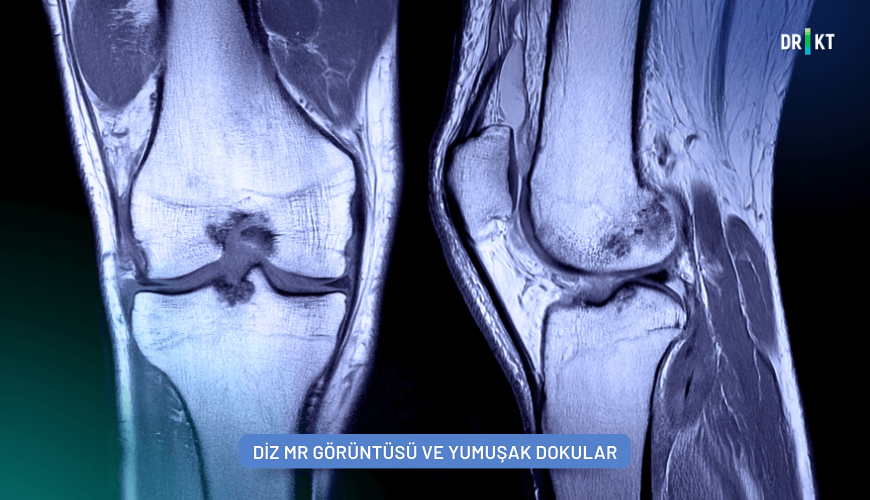

MR çekimi, ortopedik sorunları teşhis ve tedavi etmek için kullanılan önemli yöntemlerden biridir. Ortopedi doktorları kemikleri, kasları, bağ ve tendonları, kıkırdağı ve omurgayı etkileyen bozuklukları ve yaralanmaları doğru bir şekilde teşhis edebilmek ve uygun tedavi planı oluşturmak için MR, röntgen, bilgisayarlı tomografi (BT) gibi görüntüleme yöntemlerine başvurabilirler (Resim 3).

MR çekimi ile yumuşak dokuların ve kemik yapılarının güvenilir ve ayrıntılı görüntüleri elde edilir. Böylece sorunlu bir kas, bağ, tendon veya kıkırdak teşhis edilebilir. Ayrıca kireçlenme, bel fıtığı, kalça veya pelvik problemler gibi sorunlar tanımlanabilir.